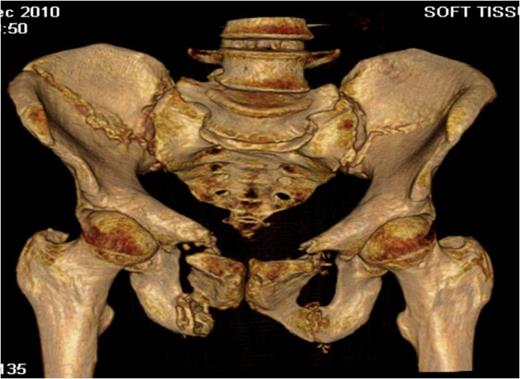

Coronal computerised tomography (CT) image demonstrating bilateral posterior iliac wing fractures and sacro-iliac joint disruption

Three-dimensional CT reconstruction showing both the bilateral crescent and superior and inferior pubic rami fractures